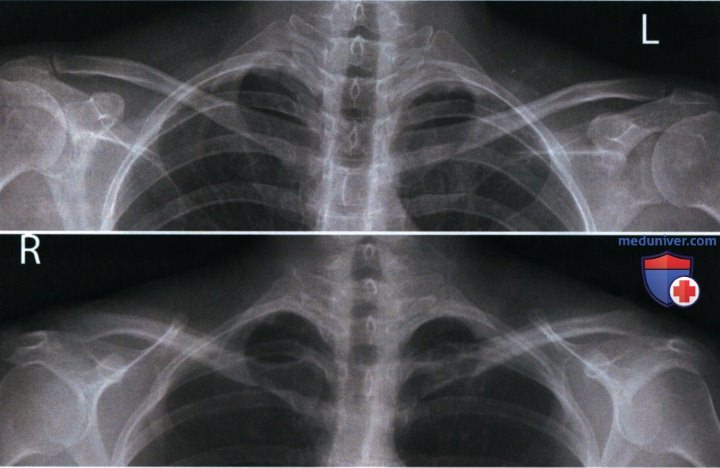

Рентгеновские технологии: усиленные экраны 35x35